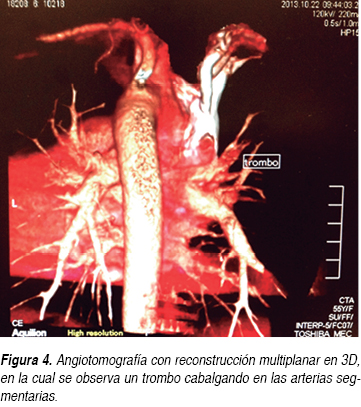

Durante su estancia hospitalaria la paciente presentó mejoría clínica, disminuyendo las cifras de presión arterial a valores normales tras ajustar el tratamiento antihipertensivo con losartán, nifedipino de liberación prolongada, nitratos orales, hipolipemiantes orales, sulfonilurea y metformina. Se incrementó la dosis de warfarina desde su ingreso a piso. Posteriormente, tras la desaparición del dolor subesternal y con la disminución de la disnea, se le pidió una ecografía de cuatro extremidades para ser realizada en un hospital de tercer nivel, sin embargo, sólo se reportó la ecografía Doppler color con enfoque en sistema venoso de miembros inferiores, sin documentarse anormalidades significativas que indicaran trombosis venosa profunda (TVP) en miembros inferiores; aunque cabe aclarar que clínicamente no presentaba dolor o datos sugestivos de tromboflebitis en extremidades superiores. Posteriormente se le solicitó a la paciente una angiotomografía de arteria pulmonar (Figuras 3 y 4), donde se demostró la presencia de un trombo (infarto pulmonar) en las ramas segmentarias de la arteria pulmonar superior derecha con datos de canalización parcial y sin imagen de semiluna, la cual orientó a pensar en un trombo crónico. No se reportaron anormalidades en el FVCI (Figura 5). La paciente fue egresada por mejoría clínica cinco días después de su hospitalización y la relación internacional normalizada (INR) a su egreso hospitalario se reportó en 3.5.